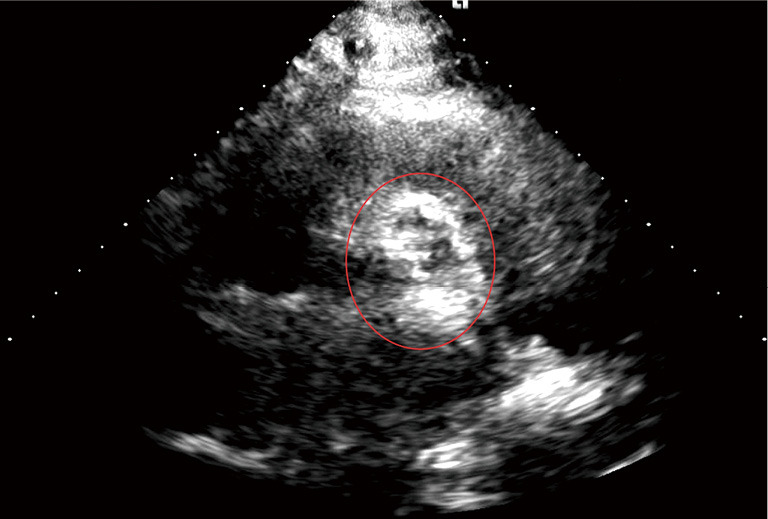

背景:超声心动图被广泛用于评估主动脉瓣狭窄(AS),但可能产生不一致的结果,导致AS严重程度的不确定性和进一步诊断的必要性。本回顾性研究旨在评估一种新的基于超声心动图的标志物,信号强度系数(SIC),其在准确识别和量化AS中钙的潜力,增强无创诊断方法。方法:在2022年5月至2023年10月期间,回顾性评估了112例以前被超声心动图认为是严重的AS,以及50例轻度或中度AS,均来自斯洛伐克科西采的东斯洛伐克心血管疾病研究所。利用ImageJ软件,基于超声信号在主动脉瓣界面处的强度分布,定量分析了超声信号在主动脉瓣界面处的强度分布。生成像素强度直方图来测量SIC,并与超声心动图变量进行比较。为了解释超声心动图图像中不同采集设置(其中最高强度对应于钙)引起的亮度变化,已经实现了自适应图像二值化。然后,交互选择和提取含钙的感兴趣区域(ROI)。这个过程可以计算钙像素数,代表钙的空间数量。本研究采用多元逻辑回归,采用逆向消去和逐步回归技术。使用受试者工作特征(ROC)曲线来评估模型预测AS严重程度的性能,并确定最佳分界点。结果:SIC是as严重程度的重要预测因子,比值比(OR)为0.021[95%可信区间(CI): 0.004-0.295, P=0.008]。将SIC与标准超声心动图参数合并到模型中,c -统计量/ROC面积从0.7023显著提高到0.8083 (P=0.01)。结论:SIC作为一种额外的基于超声心动图的标志物,在增强as严重程度检测方面表现出希望。

Methods: Between May 2022 and October 2023, 112 cases of AS that were previously considered severe by echocardiography were retrospectively evaluated, as well as a group of 50 cases of mild or moderate AS, both at the Eastern Slovak Institute of Cardiovascular Diseases in Kosice, Slovakia. Utilizing ImageJ software, we quantified the SIC based on ultrasonic signal intensity distribution at the aortic valve's interface. Pixel intensity histograms were generated to measure the SIC, and it was compared with echocardiographic variables. To account for variations in brightness due to differing acquisition settings in echocardiography images (where the highest intensity corresponds to calcium), adaptive image binarization has been implemented. Subsequently, the region of interest (ROI) containing calcium was interactively selected and extracted. This process enables the calculation of a calcium pixel count, representing the spatial quantity of calcium. This study employed multivariate logistic regression using backward elimination and stepwise techniques. Receiver operating characteristic (ROC) curves were utilized to assess the model's performance in predicting AS severity and to determine the optimal cut-off point.